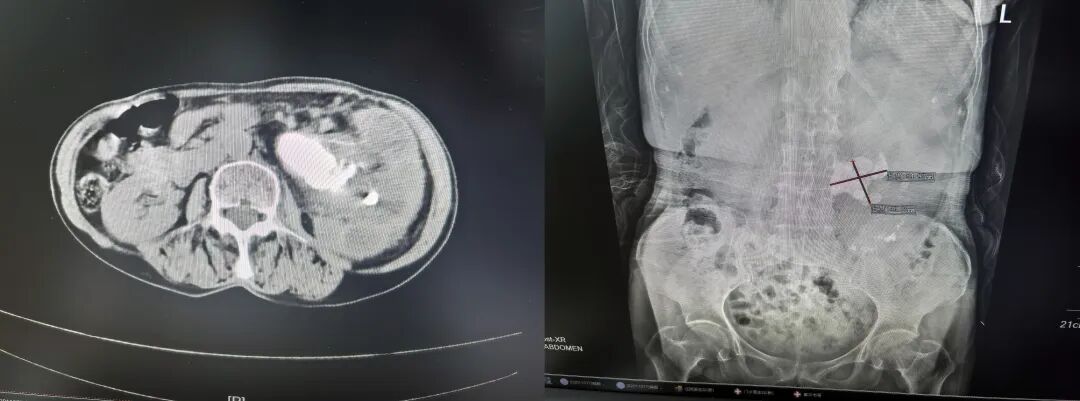

73岁邓女士慕名来到我院就诊入院后,CT显示左肾存在约55毫米×46毫米的巨大结石,合并重度积水、感染及中度贫血。科室高度重视,先期为其行“经皮肾造口术+输尿管支架置入术”,术中引流出大量黄白色脓性尿液,明确“左肾积脓”诊断。经抗感染与充分引流,由泌尿外科团队成功实施“经皮肾镜超声碎石取石术+脓苔清除术”,彻底清除结石。术后在护理团队悉心照料下,邓女士恢复良好,腰痛消失。